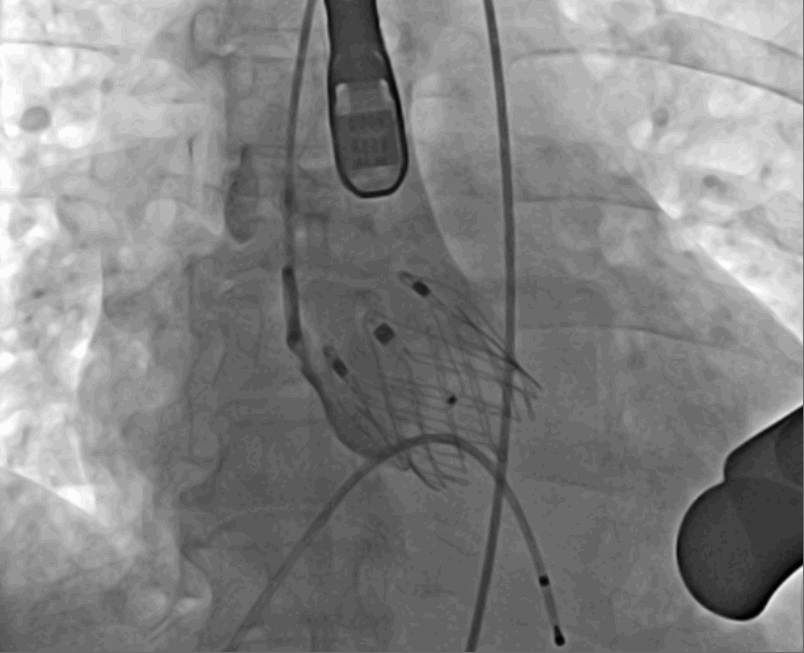

術中釋放定位鍵后DSA影像圖

術中瓣膜釋放過程